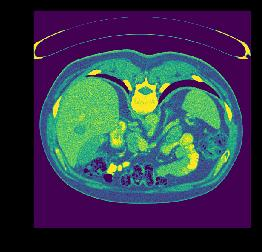

plt.imshow(data1[100,:,:]) # 对第100张slice可视化

plt.show()

volume-10.nii (221, 512, 512) 200